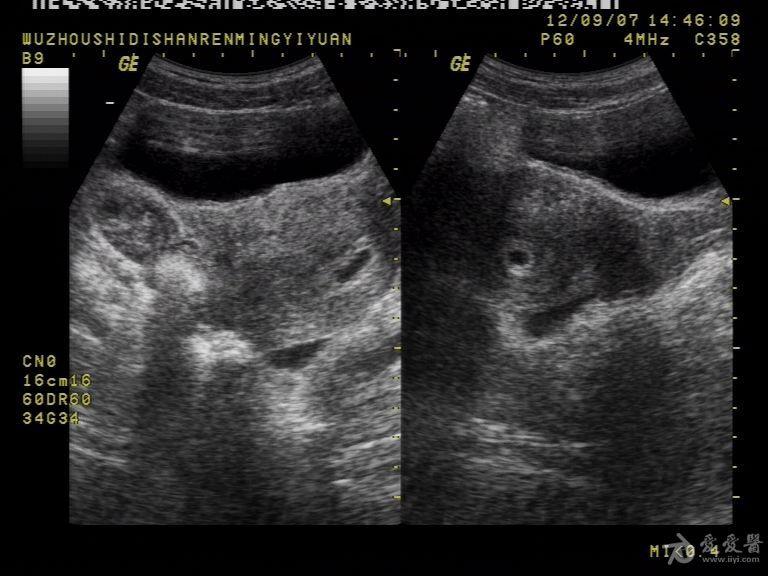

一例宫内孕合并宫外孕的彩超

图片尺寸1936x2592